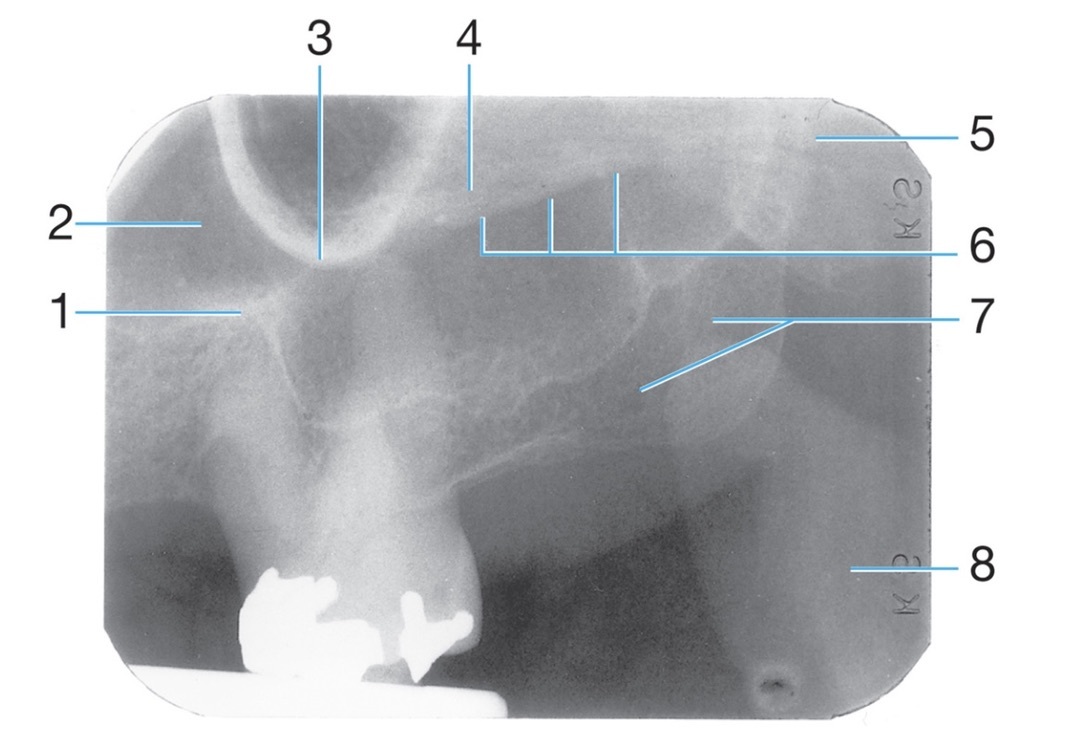

Identify the air space image #2

nasopharyngeal

Intersection of the maxillary sinus & the nasal cavity

as viewed on a dental radiograph.

Radiolucent/Radiopaque?

Inverted Y

J or U shape located above the maxillary first molars.

zygomatic process of maxilla #4

Radiopaque

Identify #1.

Border of maxillary sinus

Identify #5.

Lateral pterygoid

Identify #3.

Nutrient foramen